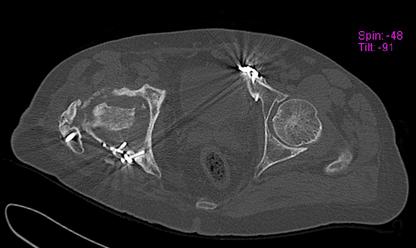

Пациент 49 лет, паровозная травма 23.2.2006, получил вертикальная нестабильное повреждение таза, разрыв левого крестцово-подвздошного сочленения, перелом лонной, седалищной костей слева, T-образный оскольчатый перелом правой вертлужной впадины с переломом заднего края, вывих правого бедра, посттравматическая пояснично-крестцовая плексопатия с обеих сторон, паралич мышц правой голени. В день травмы - вправление вывиха, скелетное вытяжение, 14.3.2006 чрескостный остеосинтез таза. 20.4.2006 остеосинтез правой вертлужной впадины пластинами, осложнившийся нагноением межмышечной гематомы правой ягодичной области. Получал консервативное лечение, было достигнуто полное заживление раны. 24.7.2006 введены илиосакральные винты слева. С декабря 2006 года и по настоящее время ходит на костылях без опоры на правую ногу. Планируется THA. Помогите определиться с вариантом костной пластики? И какую укрепляющую конструкцию использовать?

Мне кажется, будет вполне достаточно кольца Muller, костная пластика из остатков головки чипсами (нужно иметь виду, что собственной головки может не хватить и она может оказаться ненадлежащего качества, поэтому лучше иметь запас аллокости) возможна и структурная пластика, точно алло.

Бесцементная чаша, с восстановлением нормального центра вращения и с костной аутопластикой дна впадины. А Рыков Хабаровск.

Паровозы-элктровозы. Суть не в этом. Сейчас - аутокостная реконструкция вертлужной впадины. Ало - оногда секвестрация. Не надо риска. И, есле готовы технически, эндопротезирование. Лучше бесцесентная чашка прес-фит (допустем - зимет) с дополнительной фиксацией винтами. Возможен вариант кольца Мюллеа. Операцию возможно выполнить в один либо два этапа. Первы -реконструкция вертлужной впадины,а второй - протез через 3-4 мес. Кость лучше брать из гребня, т.к. головка с некрозом-склерозом-фиброзом.